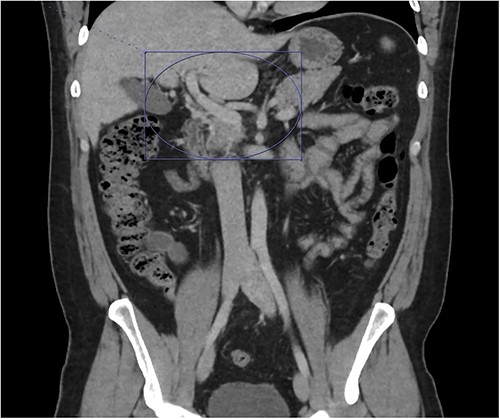

On presentation to the emergency department (ED), he was afebrile and normotensive with blood pressure in the 120s/80s though he had sinus tachycardia (heart rate 120–130 s). His abdomen was soft and diffusely tender with point tenderness at McBurney’s point and negative Rovsing’s sign. He had no signs of frank peritonitis. His complete blood count revealed leukocytosis (WBC 11K/μl), lactic acidosis (lactate 3 mmol/l), and mild transaminitis with AST 72 and ALT 101. An intravenous (IV) contrast-enhanced computed tomography scan of the abdomen/pelvis demonstrated a mildly dilated appendix (~8 mm) with surrounding fat stranding but no appendicolith, perforation, or abscess (Fig. 1). Interestingly, a partial portal vein (PV) and superior mesenteric vein (SMV) thrombosis were also noted (Fig. 2). Initial blood cultures were collected, which remained without growth.

A hyperemic and inflamed appendix can be seen without an abscess, perforation, or appendicolith.